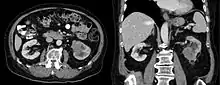

Collecting duct carcinoma

Collecting duct carcinoma (CDC) is a type of kidney cancer that originates in the papillary duct of the kidney. It is rare, accounting for 1-3% of all kidney cancers.[2] It is also recently described; a 2002 review found just 40 case reports worldwide.[3] Previously, due to its location, CDC was commonly diagnosed as renal cell carcinoma or a subtype of renal cell carcinoma.[4] However, CDC does not respond well to chemotherapy drugs used for renal cell carcinoma, and progresses and spreads more quickly.